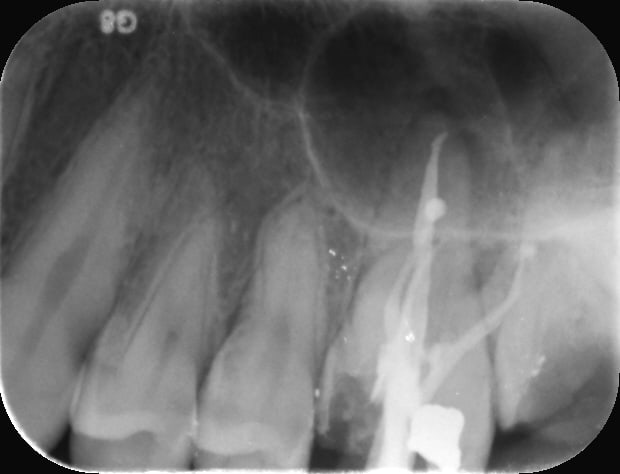

vulpi

22/02/2017 à 19h22

Bin pourquoi t'as pas fait la 7 en même temps? Pas conservable?

Joli mv2

Ben fallait que je me tape le mv2 et puis le D qui était assez courbé au 1/3 (Ca se voit pas trop sur la radio) donc j'ai pas eu le temps. Dès fois faut savoir ne pas avoir les yeux plus gros que le ventre 😉. Donc la 7 c'est pour plus tard